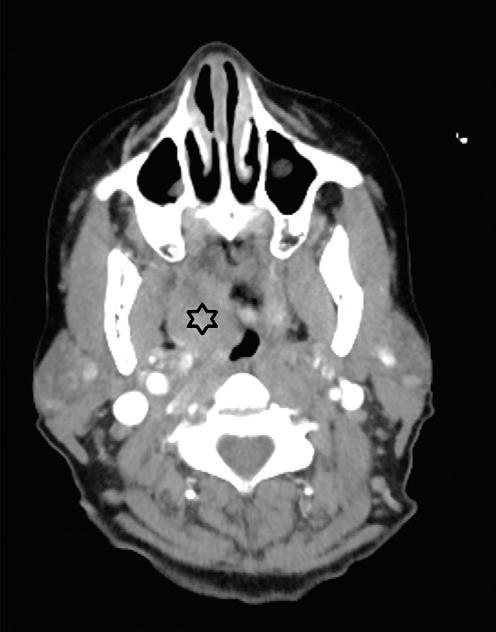

Multidisciplinary approach to diagnosis and management of lymphadenopathy in a patient with mucous membrane pemphigoid: a case report

Heba Turkstani

Eric T. Stoopler

Temitope T. Omolehinwa

Eman Alamodi

Mel Mupparapu